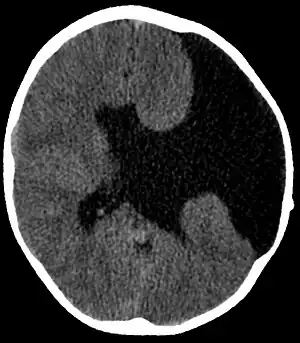

| Axial CT scan showing schizencephaly in a 6-year-old child | |

Schizencephaly (from Greek skhizein 'to split', and enkephalos 'brain')[1][2] is a rare birth defect characterized by abnormal clefts lined with grey matter that form the ependyma of the cerebral ventricles to the pia mater. These clefts can occur bilaterally or unilaterally. Common clinical features of this malformation include epilepsy, motor deficits, and psychomotor retardation.[3]